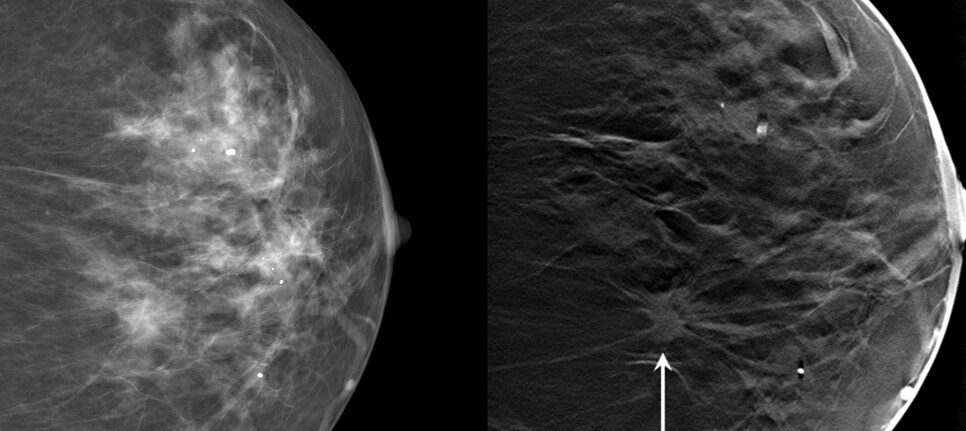

“Creating a 3D image of the breast allows us to identify a breast cancer that may be hidden on regular mammography,” explained Dr. Baker. Traditional mammography creates a two-dimensional image, and tissue at the top, middle, and bottom of the breast all overlap on this one image. 3D mammography creates a series of imaging slices at different levels of the breast. This allows breast imaging specialists to view each slice and detect breast cancer that can be hidden where the tissue overlaps on a 2D image. In addition, the 3D system can use the information it collects to make a 2D “synthetic” mammogram image with no need for additional radiation. In some cases, this 2D image can be helpful for interpreting 3D images.